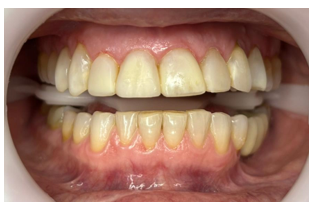

A coleta de dados foi iniciada com a realização de uma consulta inicial, na qual foi conduzida uma anamnese detalhada para levantamento do histórico médico e odontológico do paciente, bem como de suas principais queixas e expectativas em relação ao tratamento estético proposto. Em seguida, foi realizado um exame clínico minucioso com o objetivo de avaliar as facetas previamente instaladas, observando critérios como adaptação marginal, integridade do material restaurador e condições periodontais adjacentes. A saúde bucal geral do paciente também foi analisada nesta etapa, no aspecto inicial foi observado o acúmulo de biofilme causado pela má adaptação cervical, retração gengival, trincas e fraturas derivadas da oclusão desbalanceada, conforme apresenta a figura 1,2,3 e 4.

Figura 3: Vista do lado superior esquerdo.

Figura 4: Vista frontal com ênfase na região cervical do elemento 12